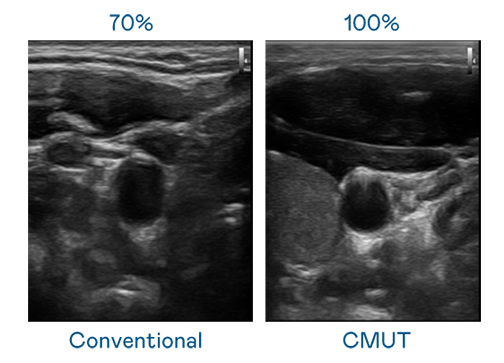

CMUT 技术是一种用电容式微机电元件来产生超音波讯号的技术。与传统 PZT 压电式技术相比,CMUT 频宽增加 30%,更宽频的超音波讯号让影像解析度大幅提升,是实现高影像品质医疗超音波扫描、促进精准医疗发展的关键技术。

大频宽带来超清晰影像

超音波影像的解析度高低,首先取决于探头能发出的讯号频宽。哈希游戏 CMUT 可提供高清晰的超音波讯号,提供高频宽、高灵敏度、影像纹理细节更高的超音波影像,协助医护人员缩短影像判读时间及利用精准的医疗影像进行诊断。